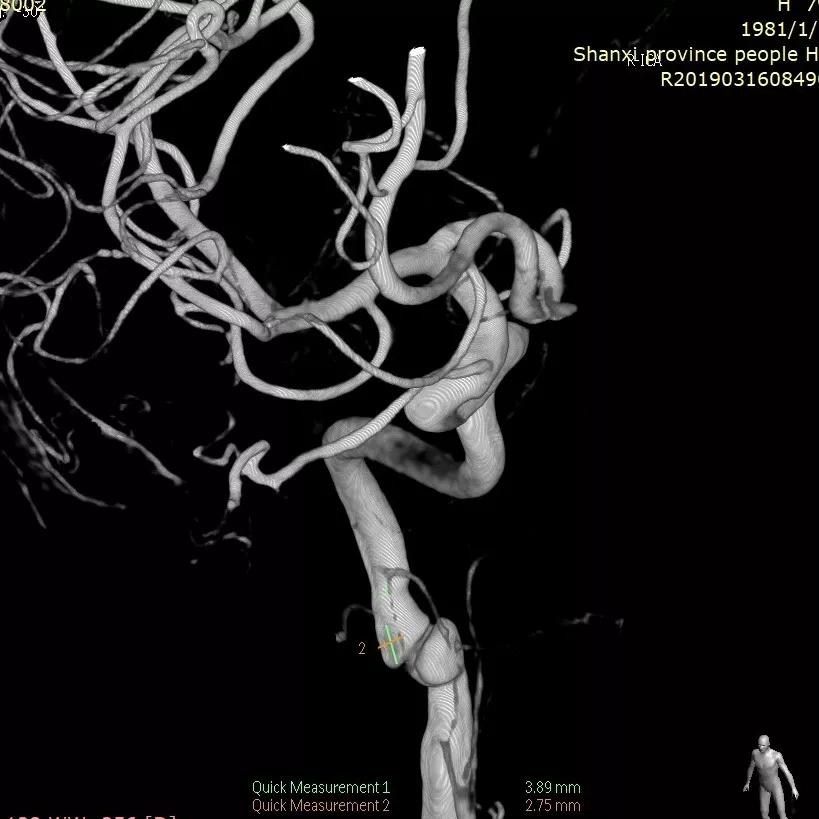

全脑血管造影可见左侧大脑中动脉动脉瘤,瘤体最大径:16.7mm,瘤颈宽:8.3mm。

Synchro 14微导丝导引支架导管,远端送入左侧中动脉下干远端困难,支架导管内穿行Tracxseed微导丝,双导丝导引支架导管顺利进入左侧中动脉下干远端,尾部链接Y阀1个,压力带1个。

经支架导管,置入Tubridge® 3.0×30mm,释放位置良好。

复查造影,动脉瘤造影剂明显滞留,各血管及分支通畅,流速正常。手术结束。